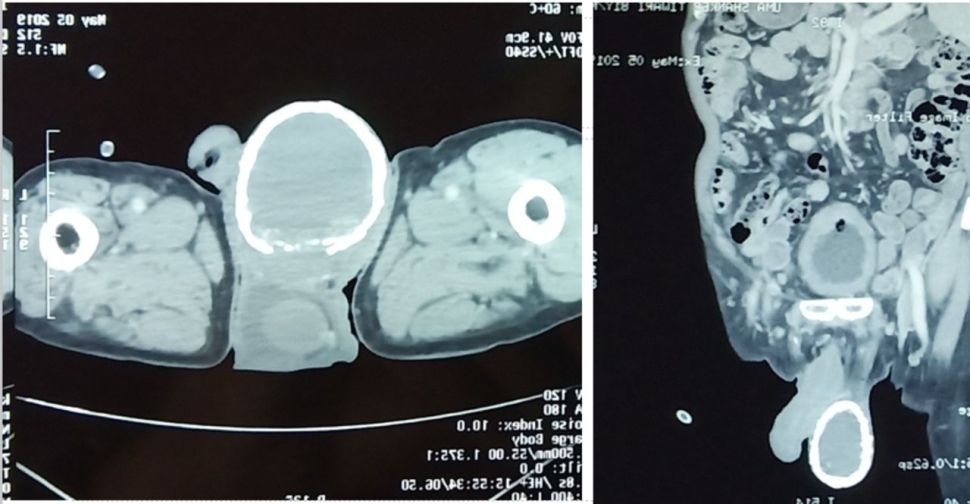

Hình chụp CT "quả trứng lạ" chứa chất lỏng, đang bị vôi hóa. Ảnh: Live Science.

Các bác sĩ phát hiện bìu bên phải của người đàn ông sưng to như quả trứng, cứng như đá. Khi quét CT, kết quả cho thấy bên trong “quả trứng” chứa đầy chất lỏng, có hiện tượng vôi hóa bởi kết tủa canxi.